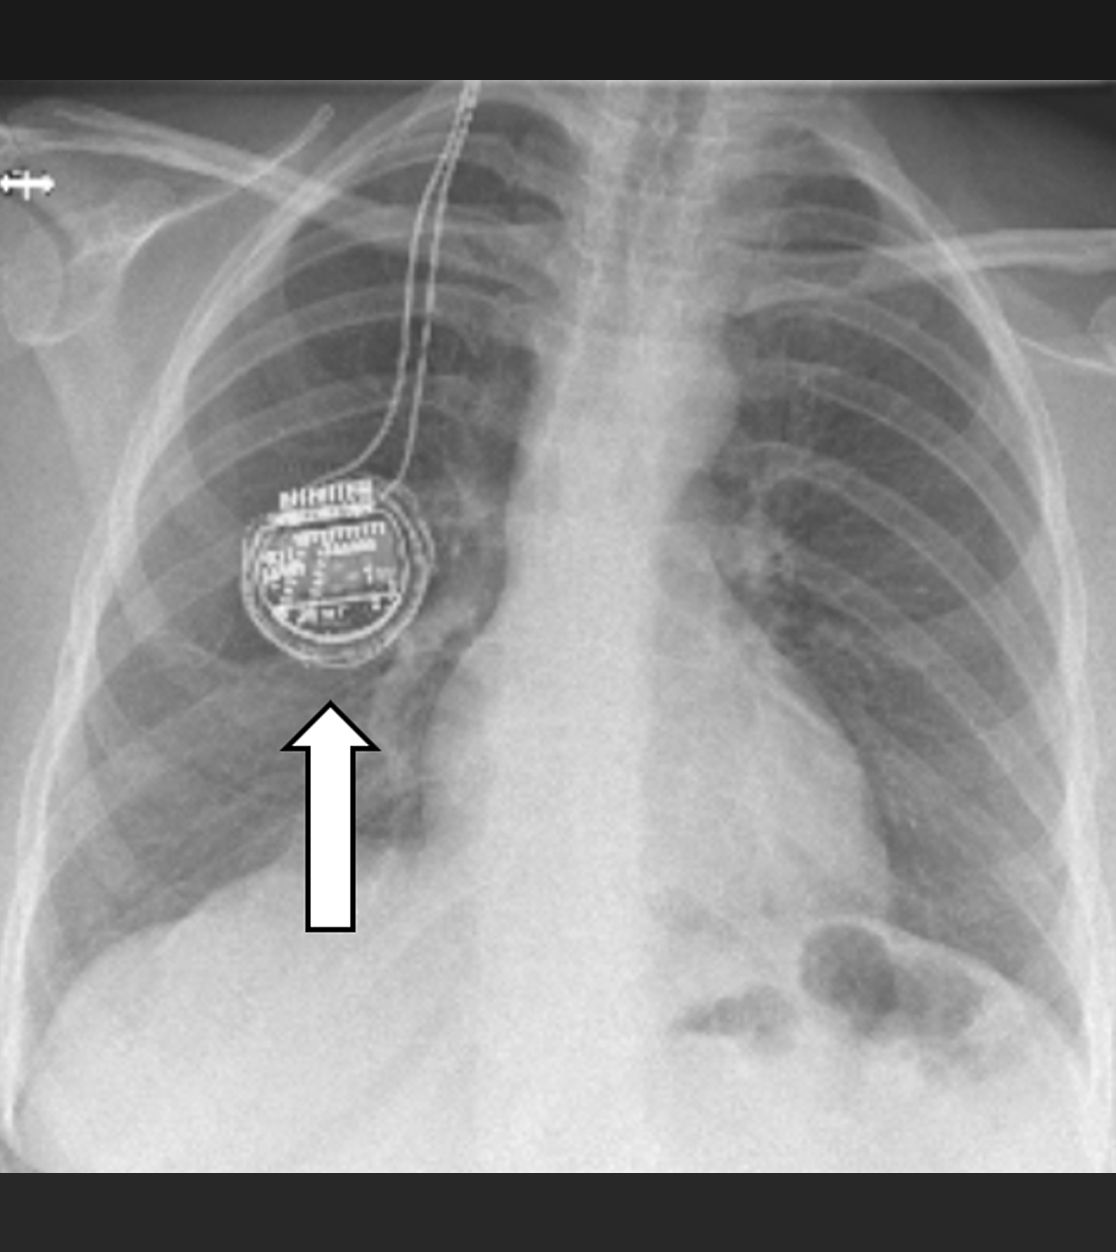

Impulsgeber im Bereich des Brustkorbs